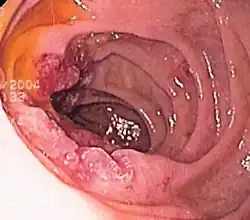

Endoscopic image of a posterior wall duodenal ulcer with a clean base, which is a common cause of upper GI hemorrhage. -